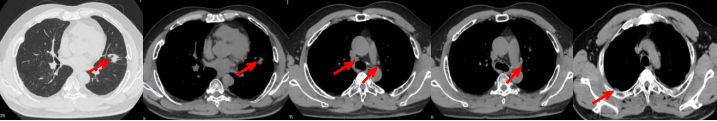

53岁男性,无吸烟饮酒史,脑血栓病史。2024年7月胸部CT:右肺下叶见一团块状软组织密度影,范围约10.8×9.0cm,边界不清,周围并见斑片状磨玻璃密度影,右肺下叶前底段支气管阻塞。纵隔及右肺门见肿大淋巴结影。考虑右肺下叶支气管肺癌。伴纵隔及右肺门淋巴结转移瘤,右下肺静脉瘤栓。2024.7.23行肺穿刺取病理:(肺)腺癌伴有神经内分泌分化。NGS基因检测:RET KIF5B exon15-RET exon12融合。PD-L1(克隆号28-8)TPS=90%。

临床诊断:右肺下叶恶性肿瘤cT4N2aM1a IVA期,肺门淋巴结继发恶性肿瘤,纵隔淋巴结继发恶性肿瘤,胸腔积液,大脑中动脉取栓术后。

治疗经过:2024.08开始口服赛普替尼(160mg,bid)。2024.09复查胸CT评效PR。2025.1复查胸CT:右肺下叶外基底段见一不规则形实性肿块,大小约94mm×87mm,边缘呈分叶状,其内密度不匀。右侧胸腔见少许水样密度影。评效PD,PFS=5个月。患者未同意再次组织活检,目前应用卡博替尼治疗,仍在随访中。治疗期间未出现毒性反应。

2024.08

2024.09评效PR

2025.01评效PD